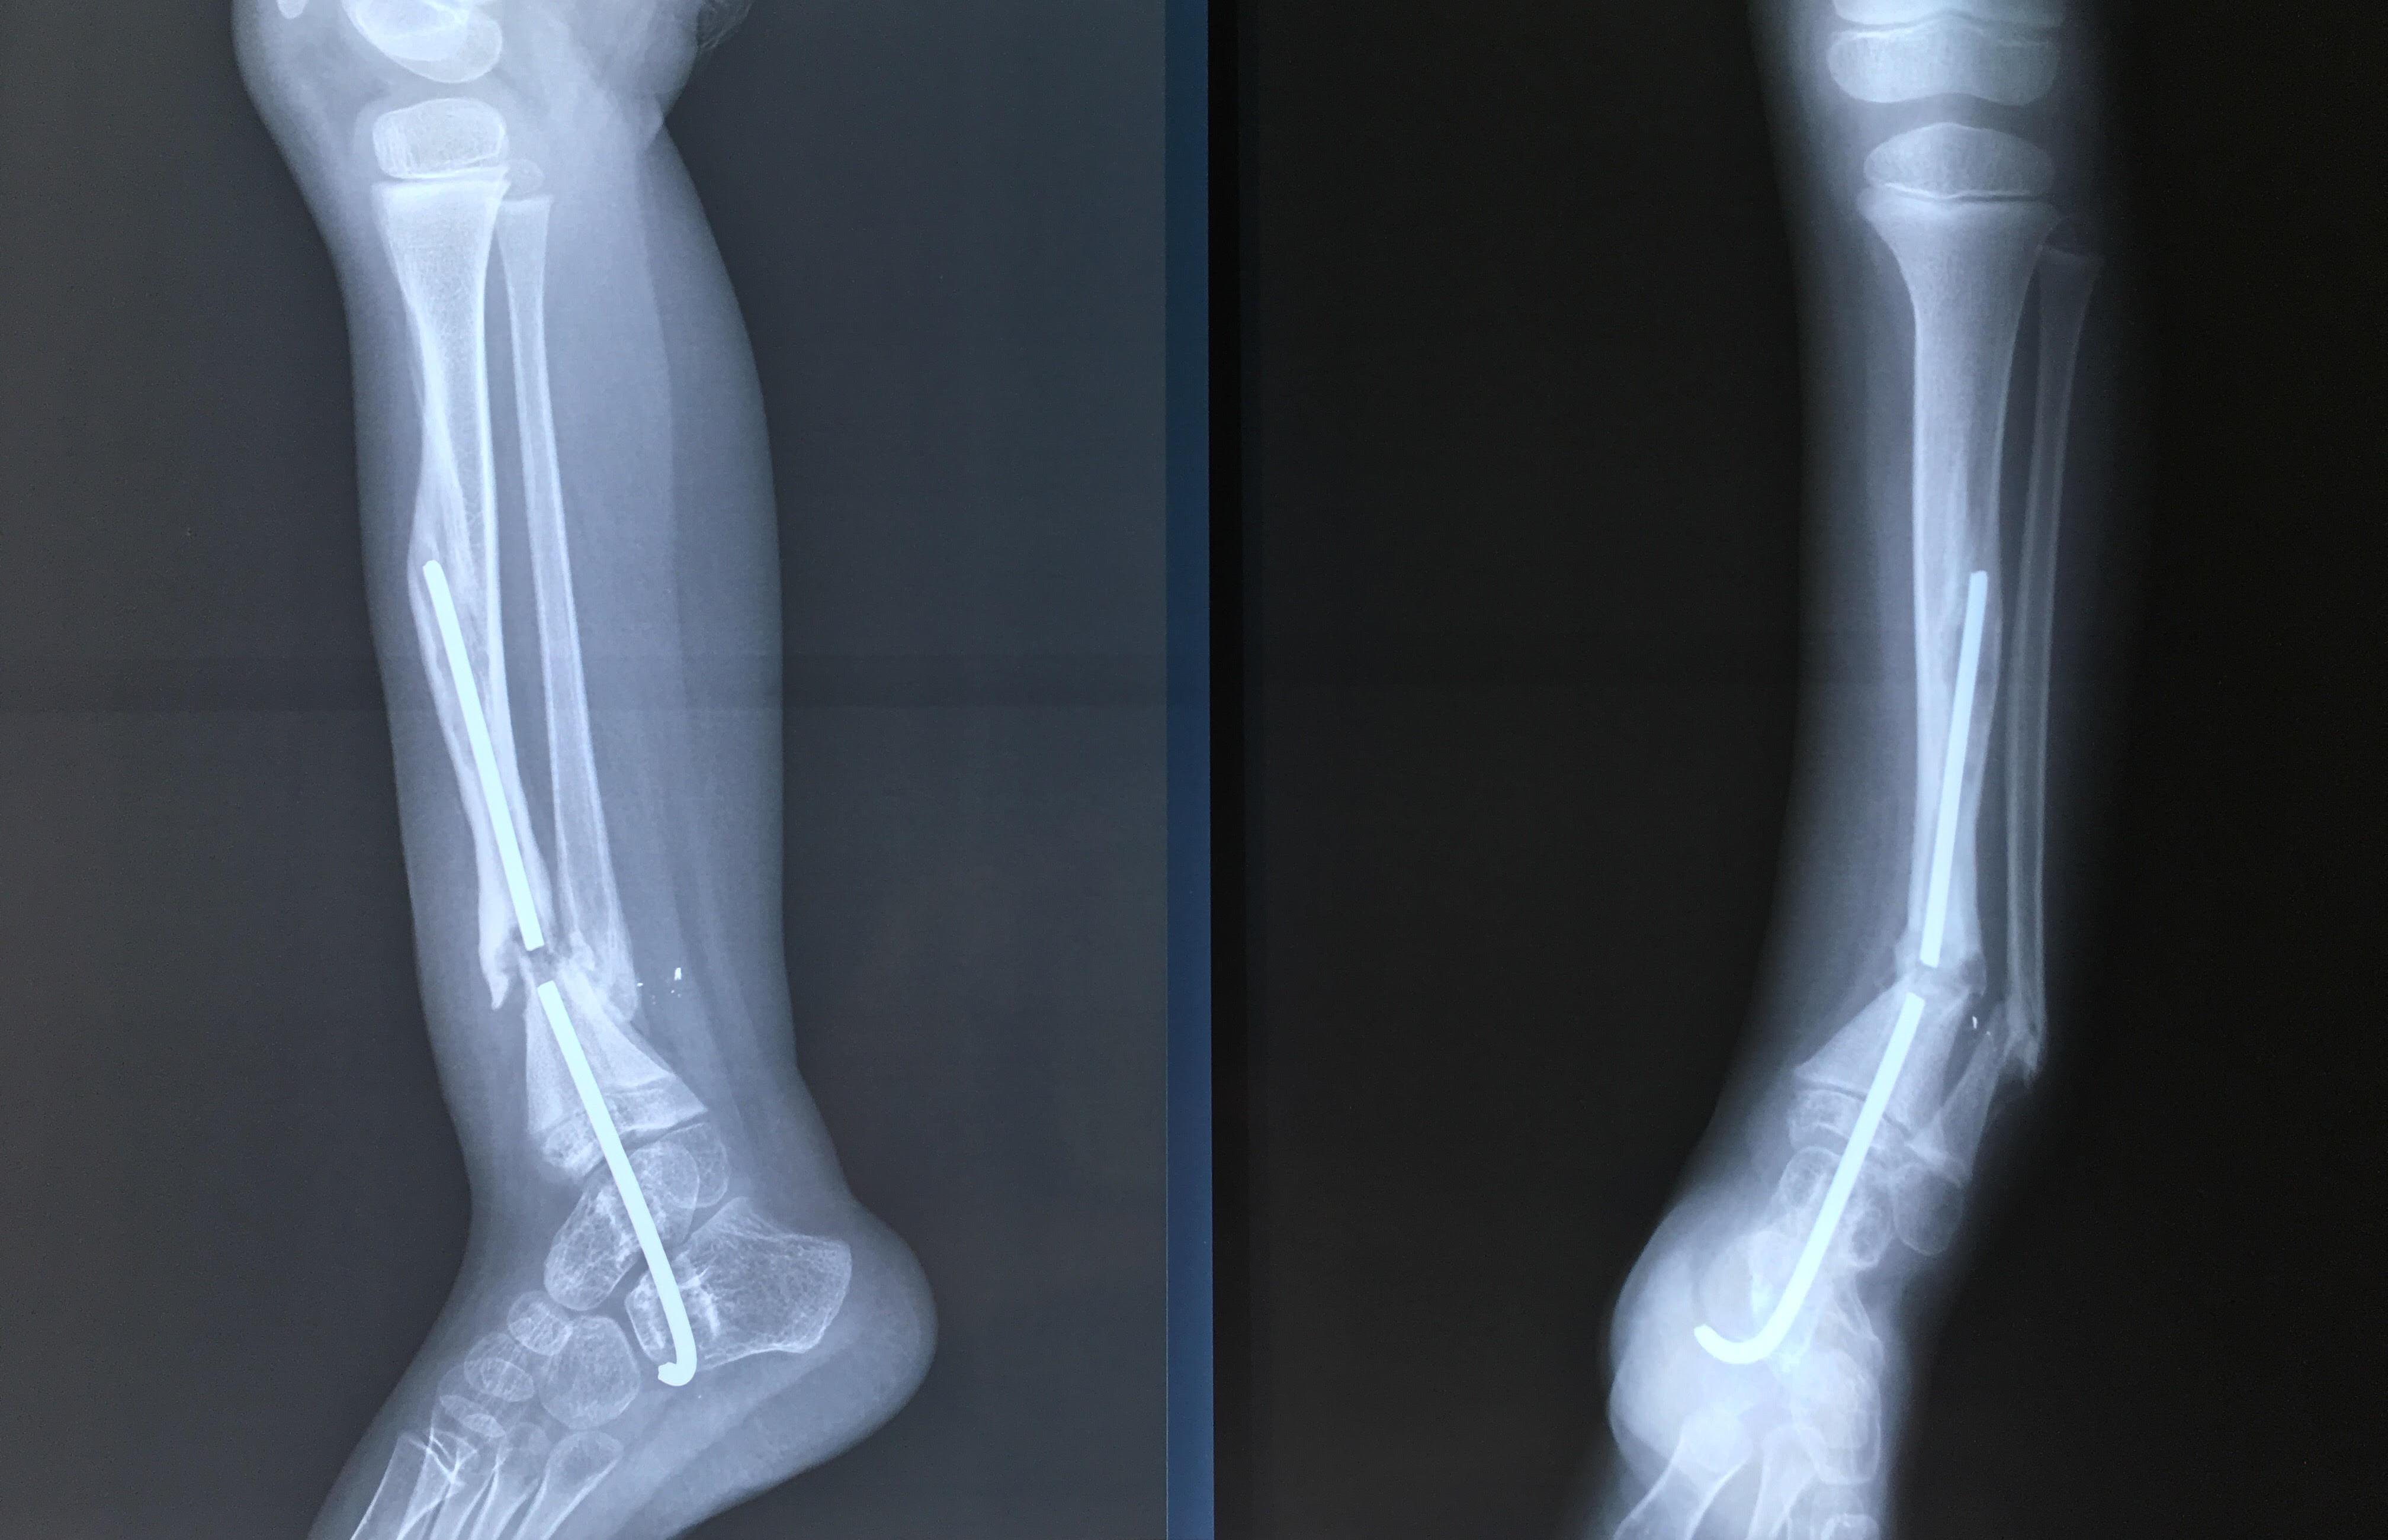

Phẫu thuật thành công ca bệnh hiếm gặp...khớp giả bẩm sinh xương chày

26/06/2019 17:00

Đã xem: 3184

Bệnh viện Chấn thương- Chỉnh hình Nghệ An, vừa phẫu thuật thành công cho bệnh nhi khớp giả bẩm sinh xương chày